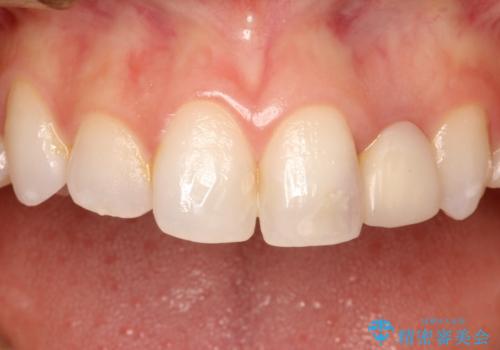

前歯の被せ物をやり替えたい

- 以前に被せ物の治療した箇所に汚れが溜まりやすいことを主訴に来院されました。

矯正治療を行なったのち、オールセラミッククラウンにて修復しております。